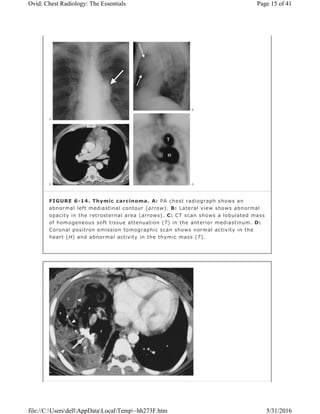

FIGURE 6-14. Thymic carcinoma. A: PA chest radiograph shows an

heart (H) and abnormal activity in the thymic mass (T).

Other less common thymic masses include cyst (Fig. 6-13), abscess,

thymolipoma, malignant lymphoma (most notably Hodgkin lymphoma), thymic

carcinoid, germ cell tumors, and thymic carcinoma (Fig. 6-14).